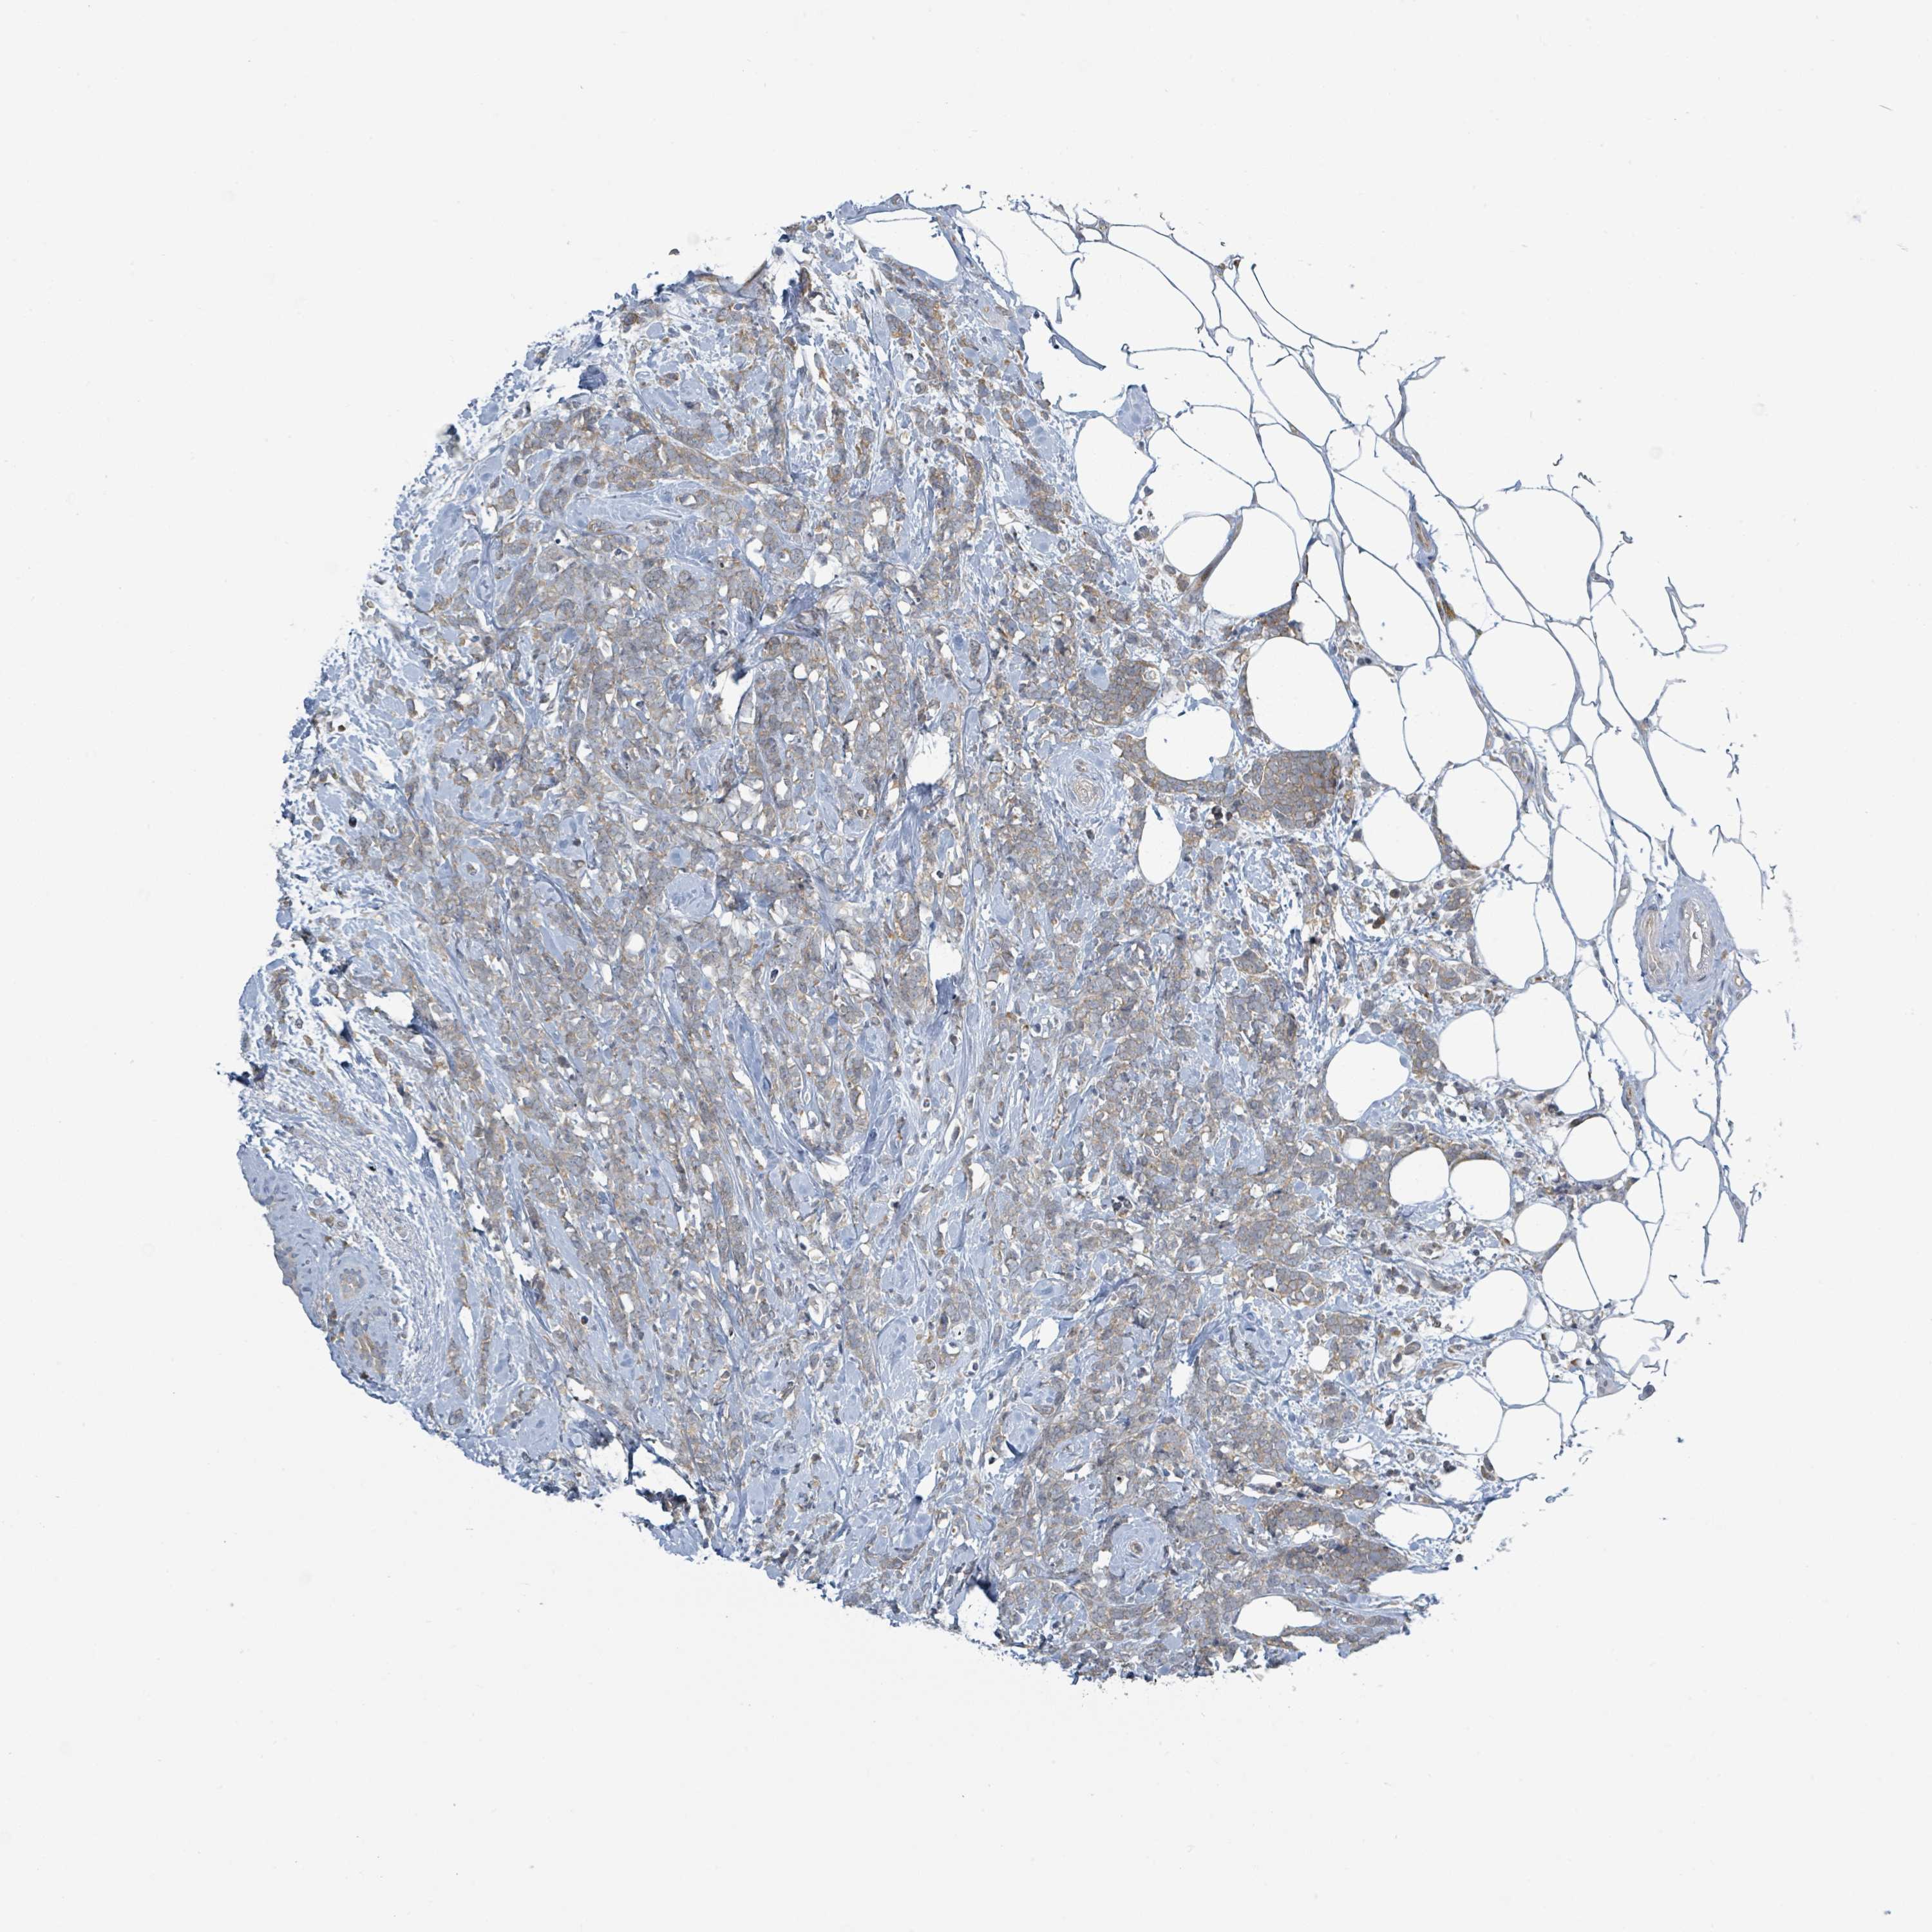

CANCER BREAST CANCER Show tissue menu

BRCA TCGA BRCA VALIDATION PROTEIN EXPRESSION

Breast cancer

Human cancer